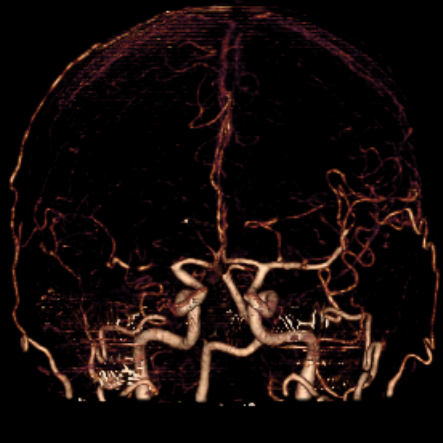

右侧MCA长节段血管变细狭长

长节段MCA血管狭长变细,尤以近端为重

重建的形态

血管形态